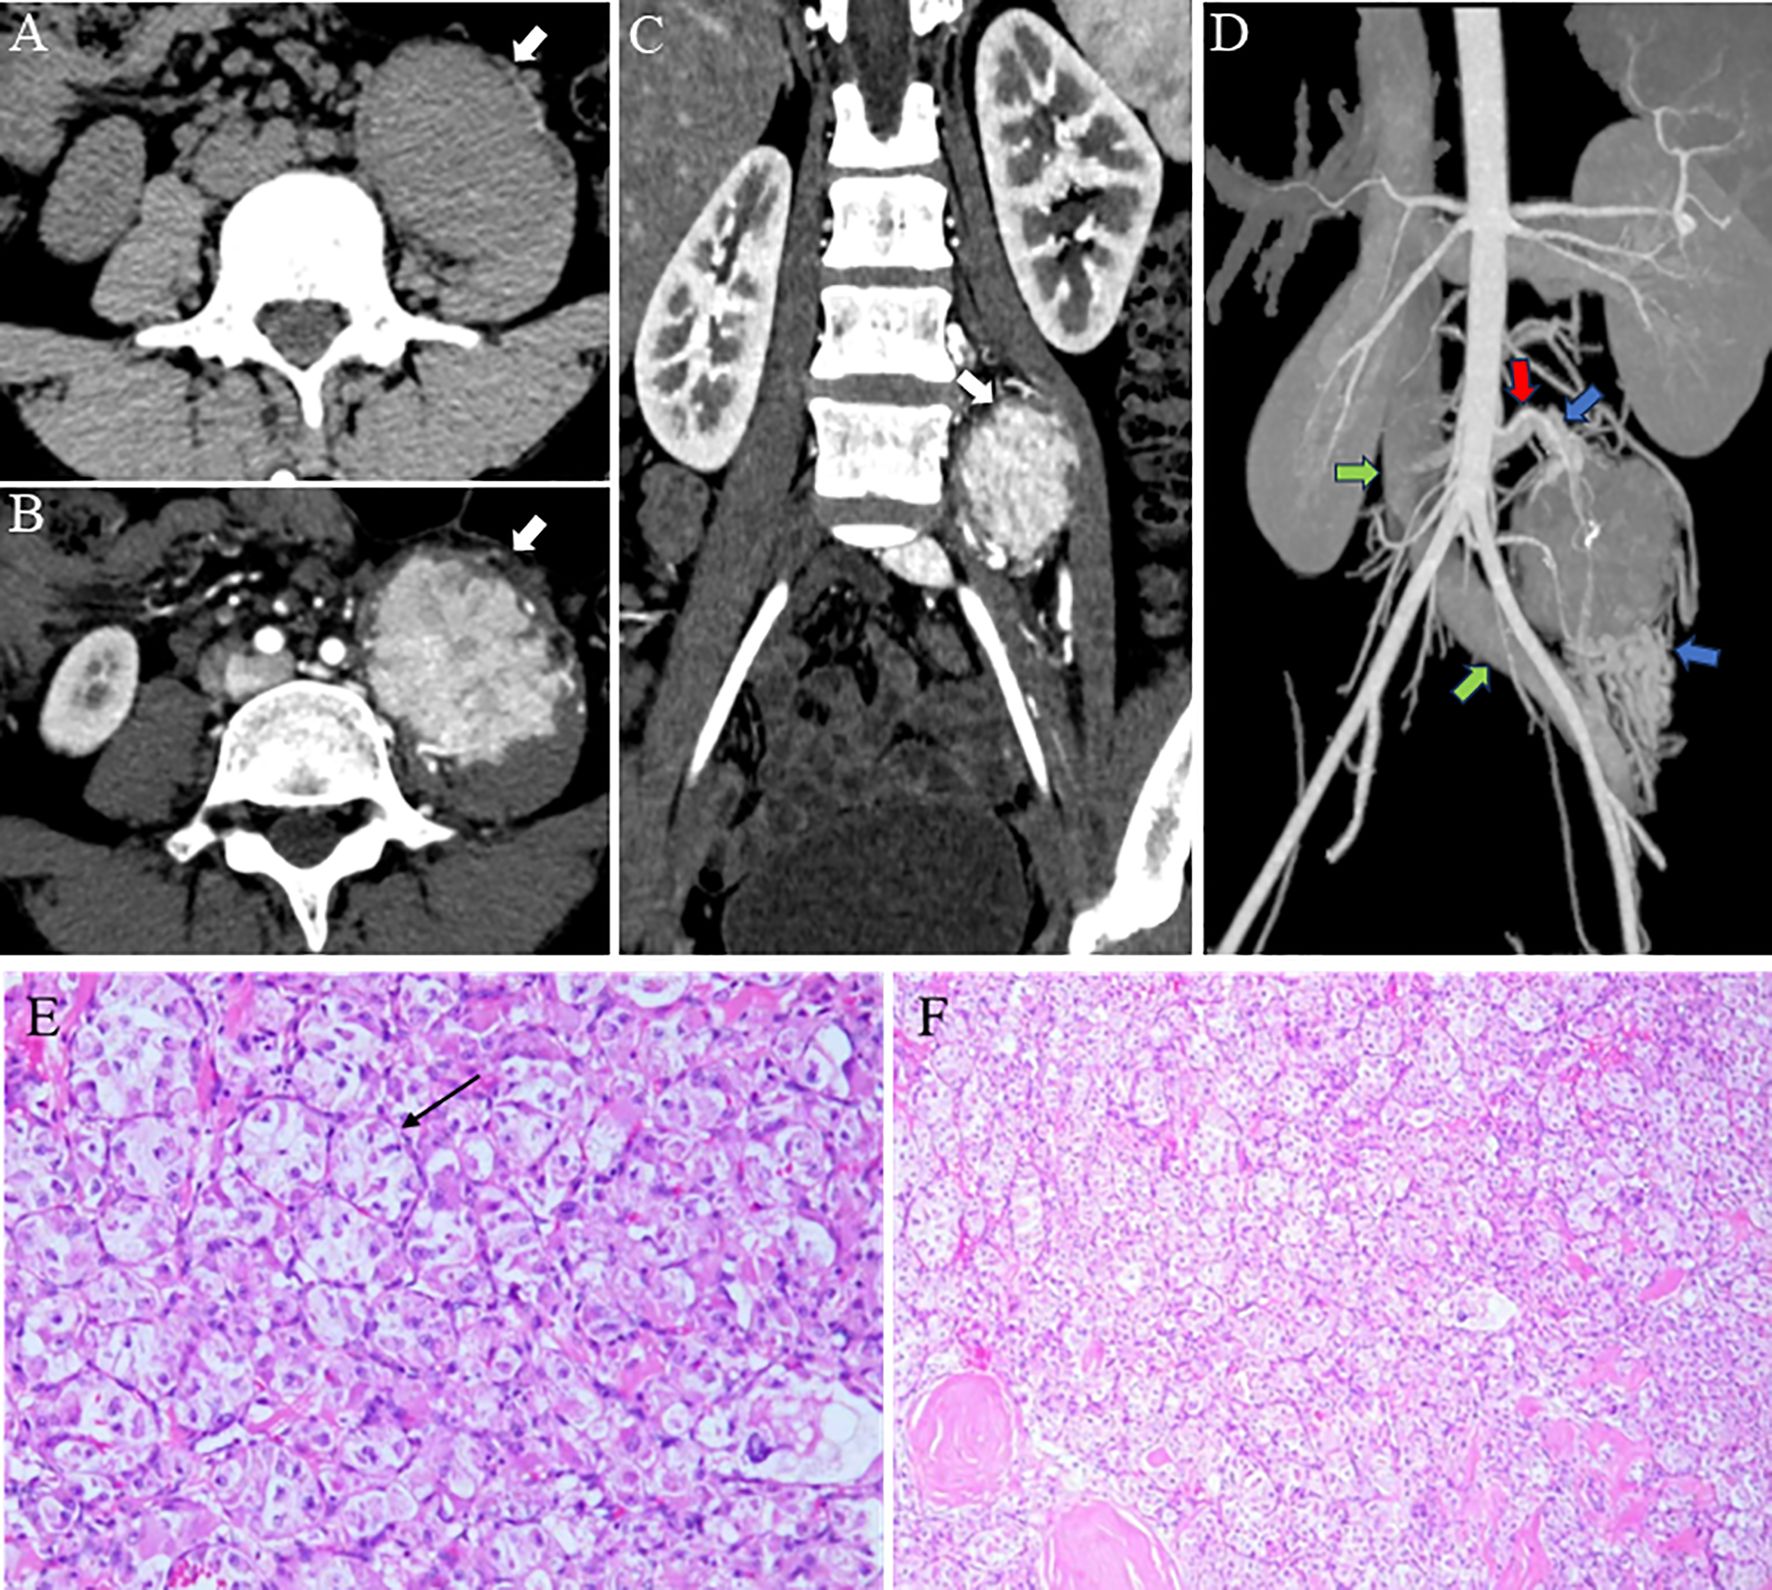

Alveolar soft part sarcoma (ASPS) is an infrequent and malignant soft tissue tumor with an elusive tissue origin. Its occurrence in the retroperitoneal psoas major muscle is extremely rare. The tumor's deep retroperitoneal location, complex anatomy, and hypervascularity pose challenges to preoperative diagnosis and surgical intervention. This case report presents a 21-year-old female diagnosed with left retroperitoneal psoas major ASPS. Advanced imaging modalities, such as computed tomography (CT) multidirectional reconstruction, magnetic resonance imaging (MRI), and three-dimensional (3D) rendering, were utilized. These imaging techniques not only clearly depicted the tumor's characteristics but also its spatial relationships with surrounding tissues and the vascular network. The detailed preoperative vascular assessment enabled the surgical team to comprehend the tumor anatomy and meticulously plan the approach, thus significantly reducing surgical risks and potential complications. The procedures and outcomes of this case offer valuable insights for clinical practice, highlighting the crucial role of imaging in the diagnosis and treatment of rare ASPS cases.